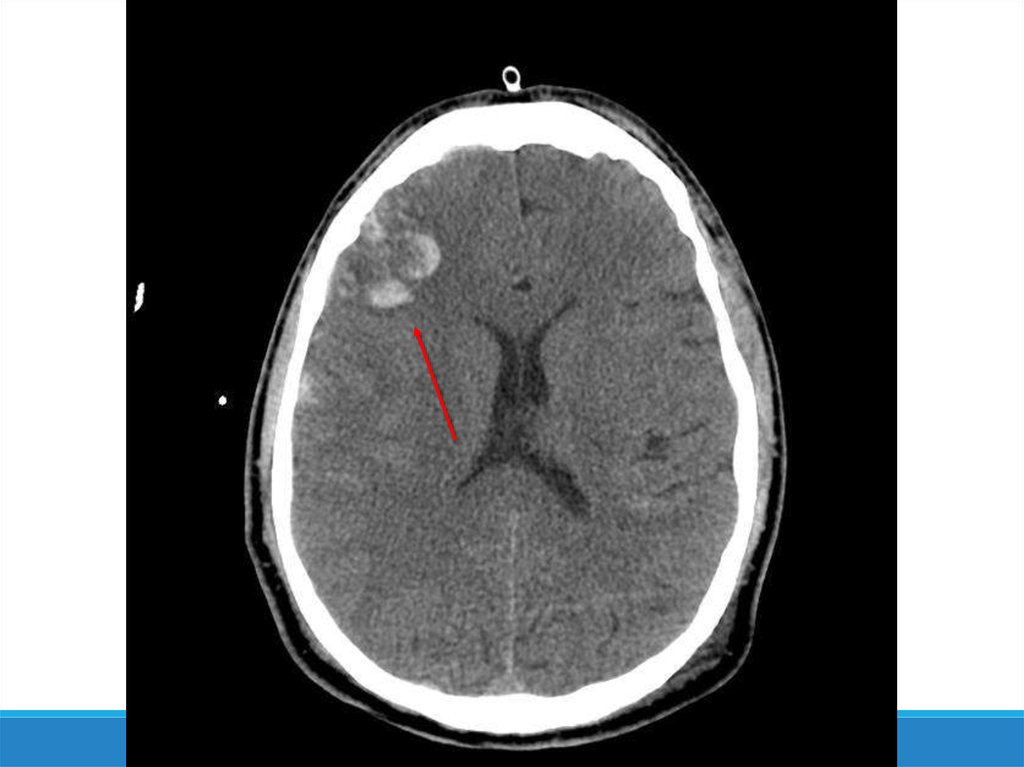

-Компьютерная томография

-Магнитно-резонансная

томография